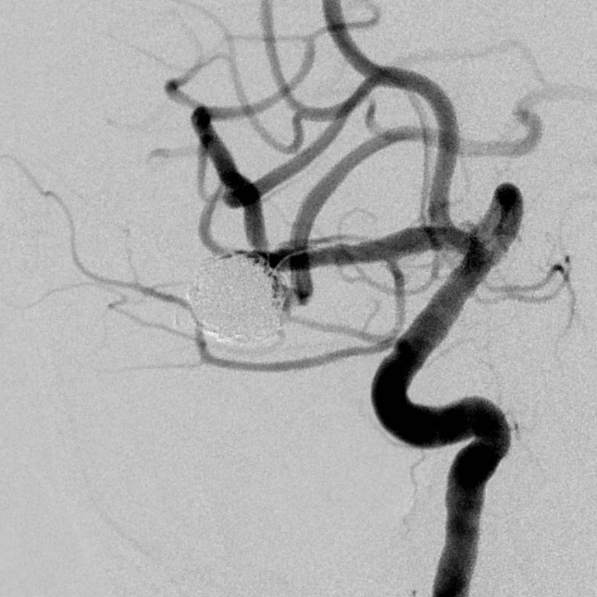

粗大分支从破裂瘤体上发出来,急性期能单纯致密栓塞吗?

最终,动脉瘤瘤体致密栓塞,各个分支保留良好